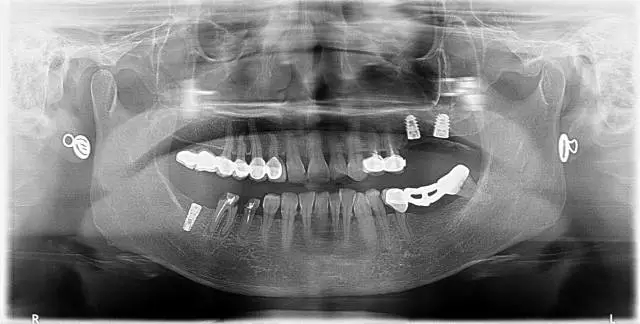

6、26,27,47種植修復(fù)(2014年1月)

4、 全景片

7、45,46,47CBCT

10、 26,27CBCT

2、治療后